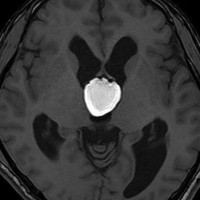

肉芽腫になってしまった第3脳室コロイドのう胞

CTでは壁が厚く高密度,MRI T2強調画像では低信号,T1強調画像では高信号です。内部に血液を含んでいるようなのう胞に見えます。のう胞の壁は非常に厚く硬いものが予想されます。閉塞性水頭症になっています。

若い男性ですが,内視鏡手術では摘出できない壁がガチガチのものでした。モンロー孔が広いので経脳梁到達法 transcallsal approachで手術しました。右前頭部から入ろうとしましたが,架橋静脈のために入れず,左前頭葉を除けて,透明中隔の正中に達しました。ところが,左の脳弓が菲薄化して広がり腫瘍の上面にみえましたから,左のモンロー孔からは摘出できませんでした。しかたがないので,右のモンロー孔から腫瘍を摘出しています。腫瘍の周囲には第3脳室脈絡叢が広範囲に癒着していました。のう胞内容は暗褐色の古い血腫でした。のう胞の壁は硬く厚い結合織で肉芽腫のような肉眼所見でした。左右の脳弓にも癒着し,内大脳静脈にも癒着していたので,その部分には皮膜を残しました。

術後のMRIです。幸い,記憶障害などの脳弓症状はでませんでしたが,かなりリスクの高い手術でした。